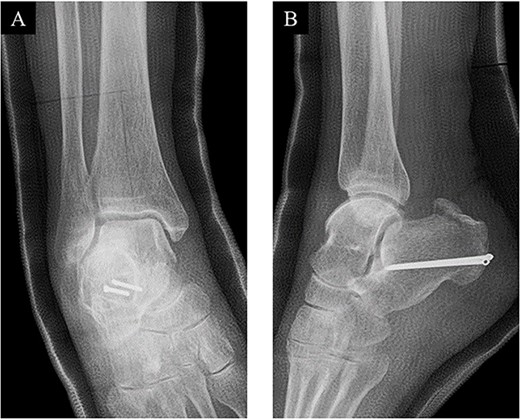

A 78-year-old woman complained of right heel pain when tripping during walking and visited to our hospital. She had medical histories such as arrhythmia, hypertension and hyperlipidemia. Physical examination revealed swelling, subcutaneous bleeding and tenderness on the posterior aspect of her heel and Thompson test was positive. Plain radiographs of the right ankle showed an avulsion fracture of the calcaneal tuberosity (Fig. 1). Non-contrast computed tomography (CT) demonstrated that the bone fragment was displaced. Based on medical histories, physical examination and image findings, we diagnosed an avulsion fracture of the calcaneal tuberosity and applied surgical treatment for the patient.

Plain radiographs of the right ankle showed no abnormal findings in (A) an anteroposterior view, but an avulsion fracture of the calcaneal tuberosity (B) a lateral view.